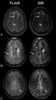

Juxtacortical chondroma